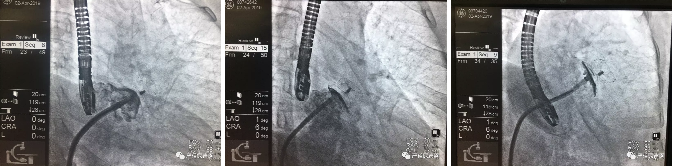

SeaLA®左心耳封堵器释放后影像图

(三位患者依次从左至右)

三名患者为两位女性和一位男性,年龄分别为67,76和59岁,分别患阵发性,持续性,阵发性心房颤动;术前经食道超声心动图示:三位患者左心耳均为单腔结构;术中在全麻下经导管植入了杭州诺茂研制的SeaLA®左心耳封堵器,三例封堵器锚定盘直径均为24mm规格,均成功一次性植入左心耳,术中牵拉测试产品锚定良好,术后超声造影均无残余分流,术后患者无不适,各项指标正常。